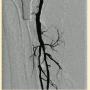

Peripheral angiography showed total occlusion of the right distal superficial femoral artery extending into the popliteal artery and into the trifurcation, with reconstitution of a peroneal and a posterior tibial. We attempted to obtain antegrade access to the lesions of the right infra-popliteal vessels (Figure 1). After failing to cross the lesion, we obtained retrograde access, puncturing from below the lesion through the posterior tibial artery near the ankle joint (Figure 2). Access was obtained and the lesion below the knee was crossed (Figure 3). Following this, the V-18 control wire (Boston Scientific) was snared from above, a CXI support catheter (CSI) was backloaded over the wire, and an antegrade Viperwire (CSI) was then placed, with removal of the retrograde sheath and wire. Atherectomy was performed with the 1.5mm Stealth 360° orbital atherectomy device (CSI) followed by balloon angioplasty with Cook, Sterling (Boston Scientific), and Chocolate (Cordis) balloon catheters. After angioplasty, significant improvement in luminal gain was noted at the expense of a dissection (Figure 4). We chose to place a Zilver PTX drug-eluting stent (Cook) within the distal superficial femoral and popliteal artery segment (Figure 5). After the procedure, the patient’s wounds completely healed. An angiogram 3 months later was performed, showing the vessels to be widely patent (Figure 6). The patient sent us a video of himself finally walking, and without pain (Video 1; online).